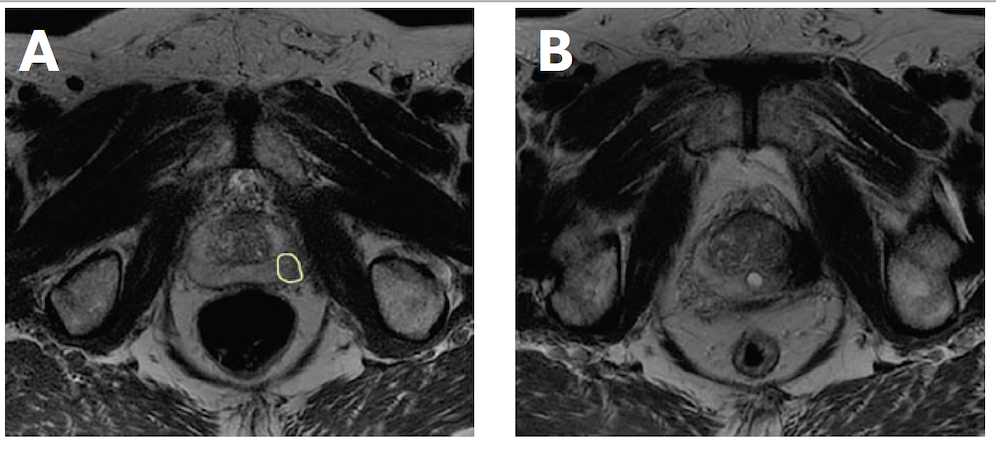

After undergoing focal therapy, patients typically undergo a posttreatment biopsy and are subsequently monitored with serial prostate-specific antigen (PSA) tests and MRI exams. Prostate cancer recurrence may be identified at any point during the follow-up after treatment. Similar to patients who are being followed on active surveillance, there are challenges classifying cancer that is detected during follow-up. Based on our experience from patients undergoing radical prostatectomy, recurrence is frequently attributed to cancers growing in the resection bed or as newly detected areas of previously occult metastases. However, from the perspective of patients undergoing focal therapy, a recurrence could be either in the previously treated area or a newly identified foci in an untreated segment of the prostate. During the posttreatment biopsy, cores are obtained from the treatment zone in addition to the remaining prostate. Figure 1 illustrates a patient who underwent focal therapy of the left lateral peripheral zone, with persistent cancer identified on the 6-month biopsy. One of the most frequently proposed criticisms of focal therapy is the potential for untreated occult cancers. Although this is a valid concern, there are several treatment options for these patients and for those who have residual cancer in the focal therapy treatment zone. Figure 2 demonstrates a patient with successful ablation of a right-sided lesion but with newly discovered occult contralateral cancer identified on the systematic biopsies. Classifying the cancer recurrence can help guide recommendations for salvage treatments.